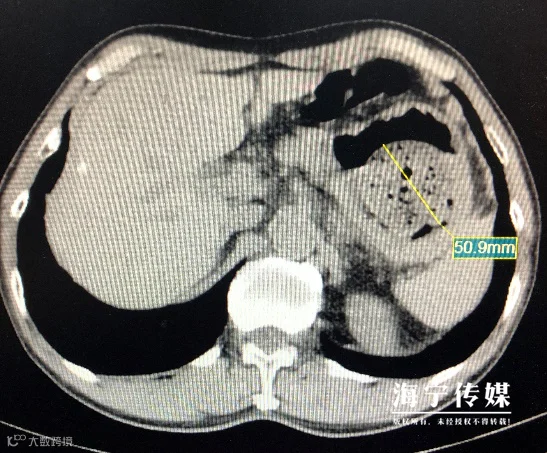

接诊的朱忠杰大夫了解孙大叔的情况后,首先给他做了腹部CT,提示胃内有一个直径约5cm高密度影。

△腹部CT提示胃内有一个直径约5cm高密度影